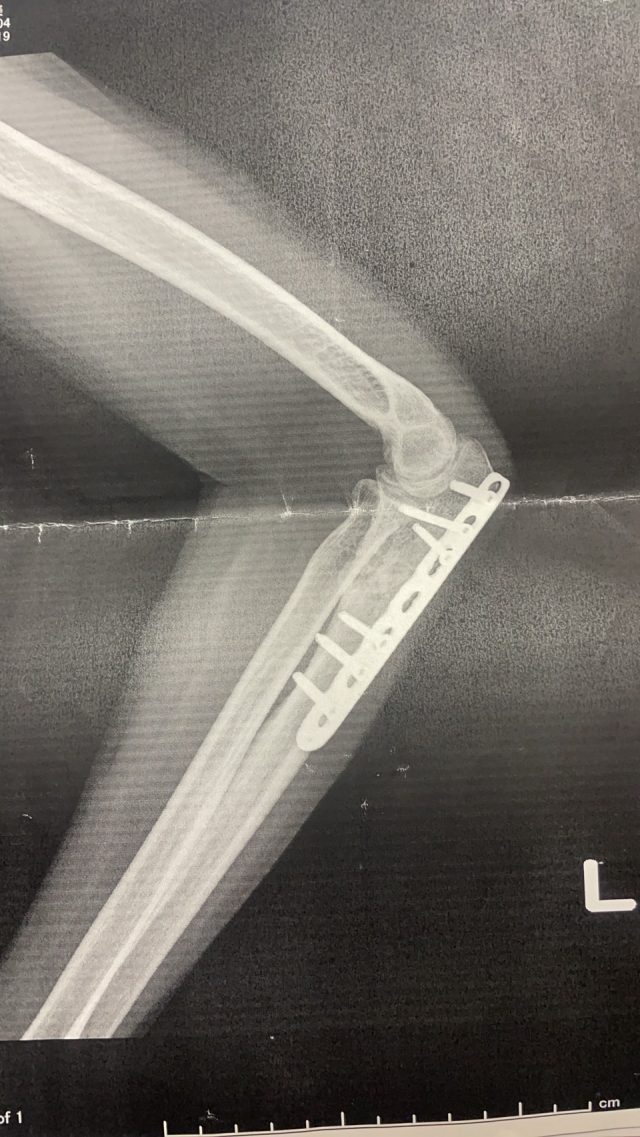

実際のレントゲン写真です。 ※掲載の許可はいただいております

実際の患者さんの写真です。 これは実際に来院された方のレントゲン写真です。 骨折後の影響で、関節の動きが制限されています